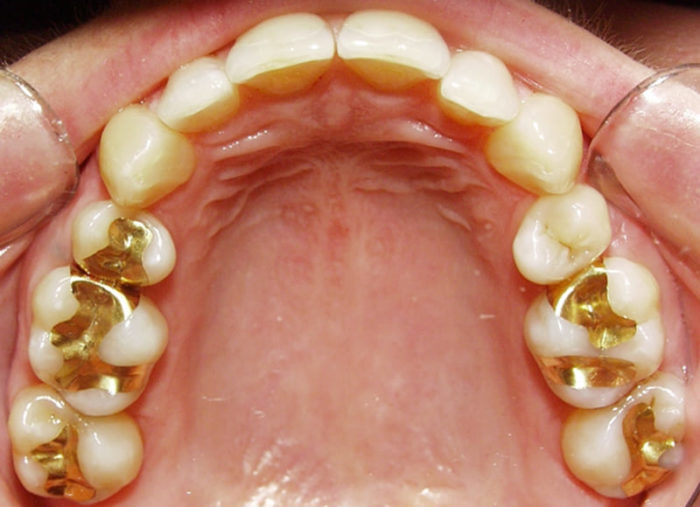

Trám răng thẩm mỹ là gì? Có những loại nào? Lưu ý gì?